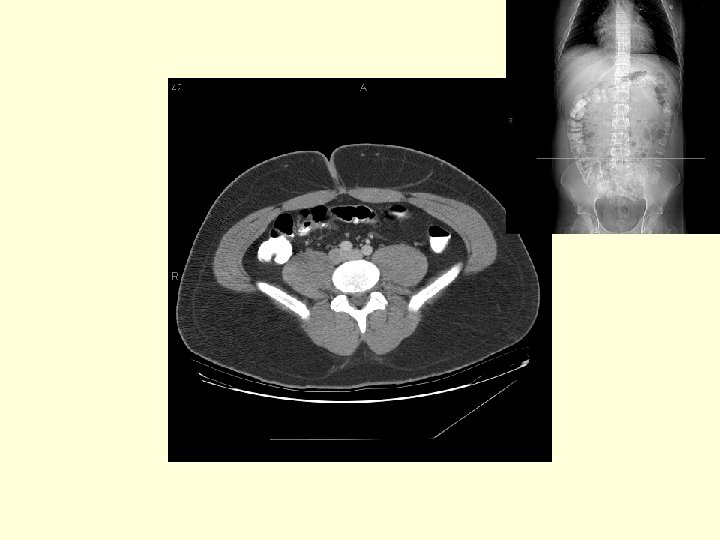

This is a patient with diverticulitis. Trace the sigmoid colon (white arrows) over the next 6 images and noted the wall thickening and the mesenteric fat stranding (circle).